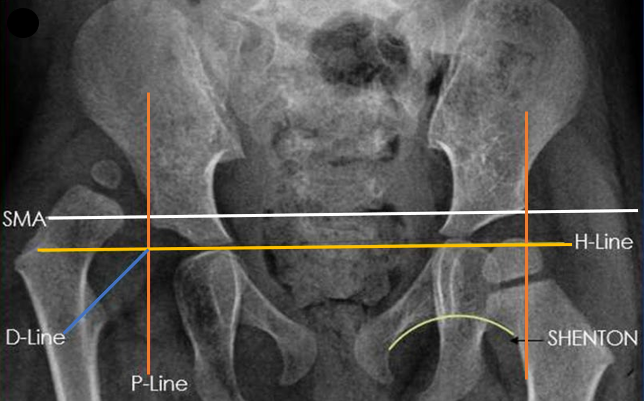

Plain radiographs are rarely used in the neonatal period or for routine early screening since the cartilaginous acetabulum and unossified femoral head will not be appreciated on the X-rays. However, it the stand imaging method used after 6 months. Commonly, done views are the antero-posterior (AP) view of pelvis with both hips (both patellae facing forwards), frog leg lateral view and rarely the Von Rosen view. The radiographic lines are described in Fig 2.

Fig 2: Pelvis with both hips antero-posterior view showing x-ray. H-line is the Hilgenreiner's line drawn from the outer margin of the acetabulum. P-line is the Perkin's line passes through the triradiate cartilage. SMA is the superior margin of acetabulum line which joins both lateral acetabular sourcils. D-line is the diagonal line from the intersection of H and P lines at 45˚. Shenton line is drawn from the inferior neck surface to the superior margin of obturator foramen.